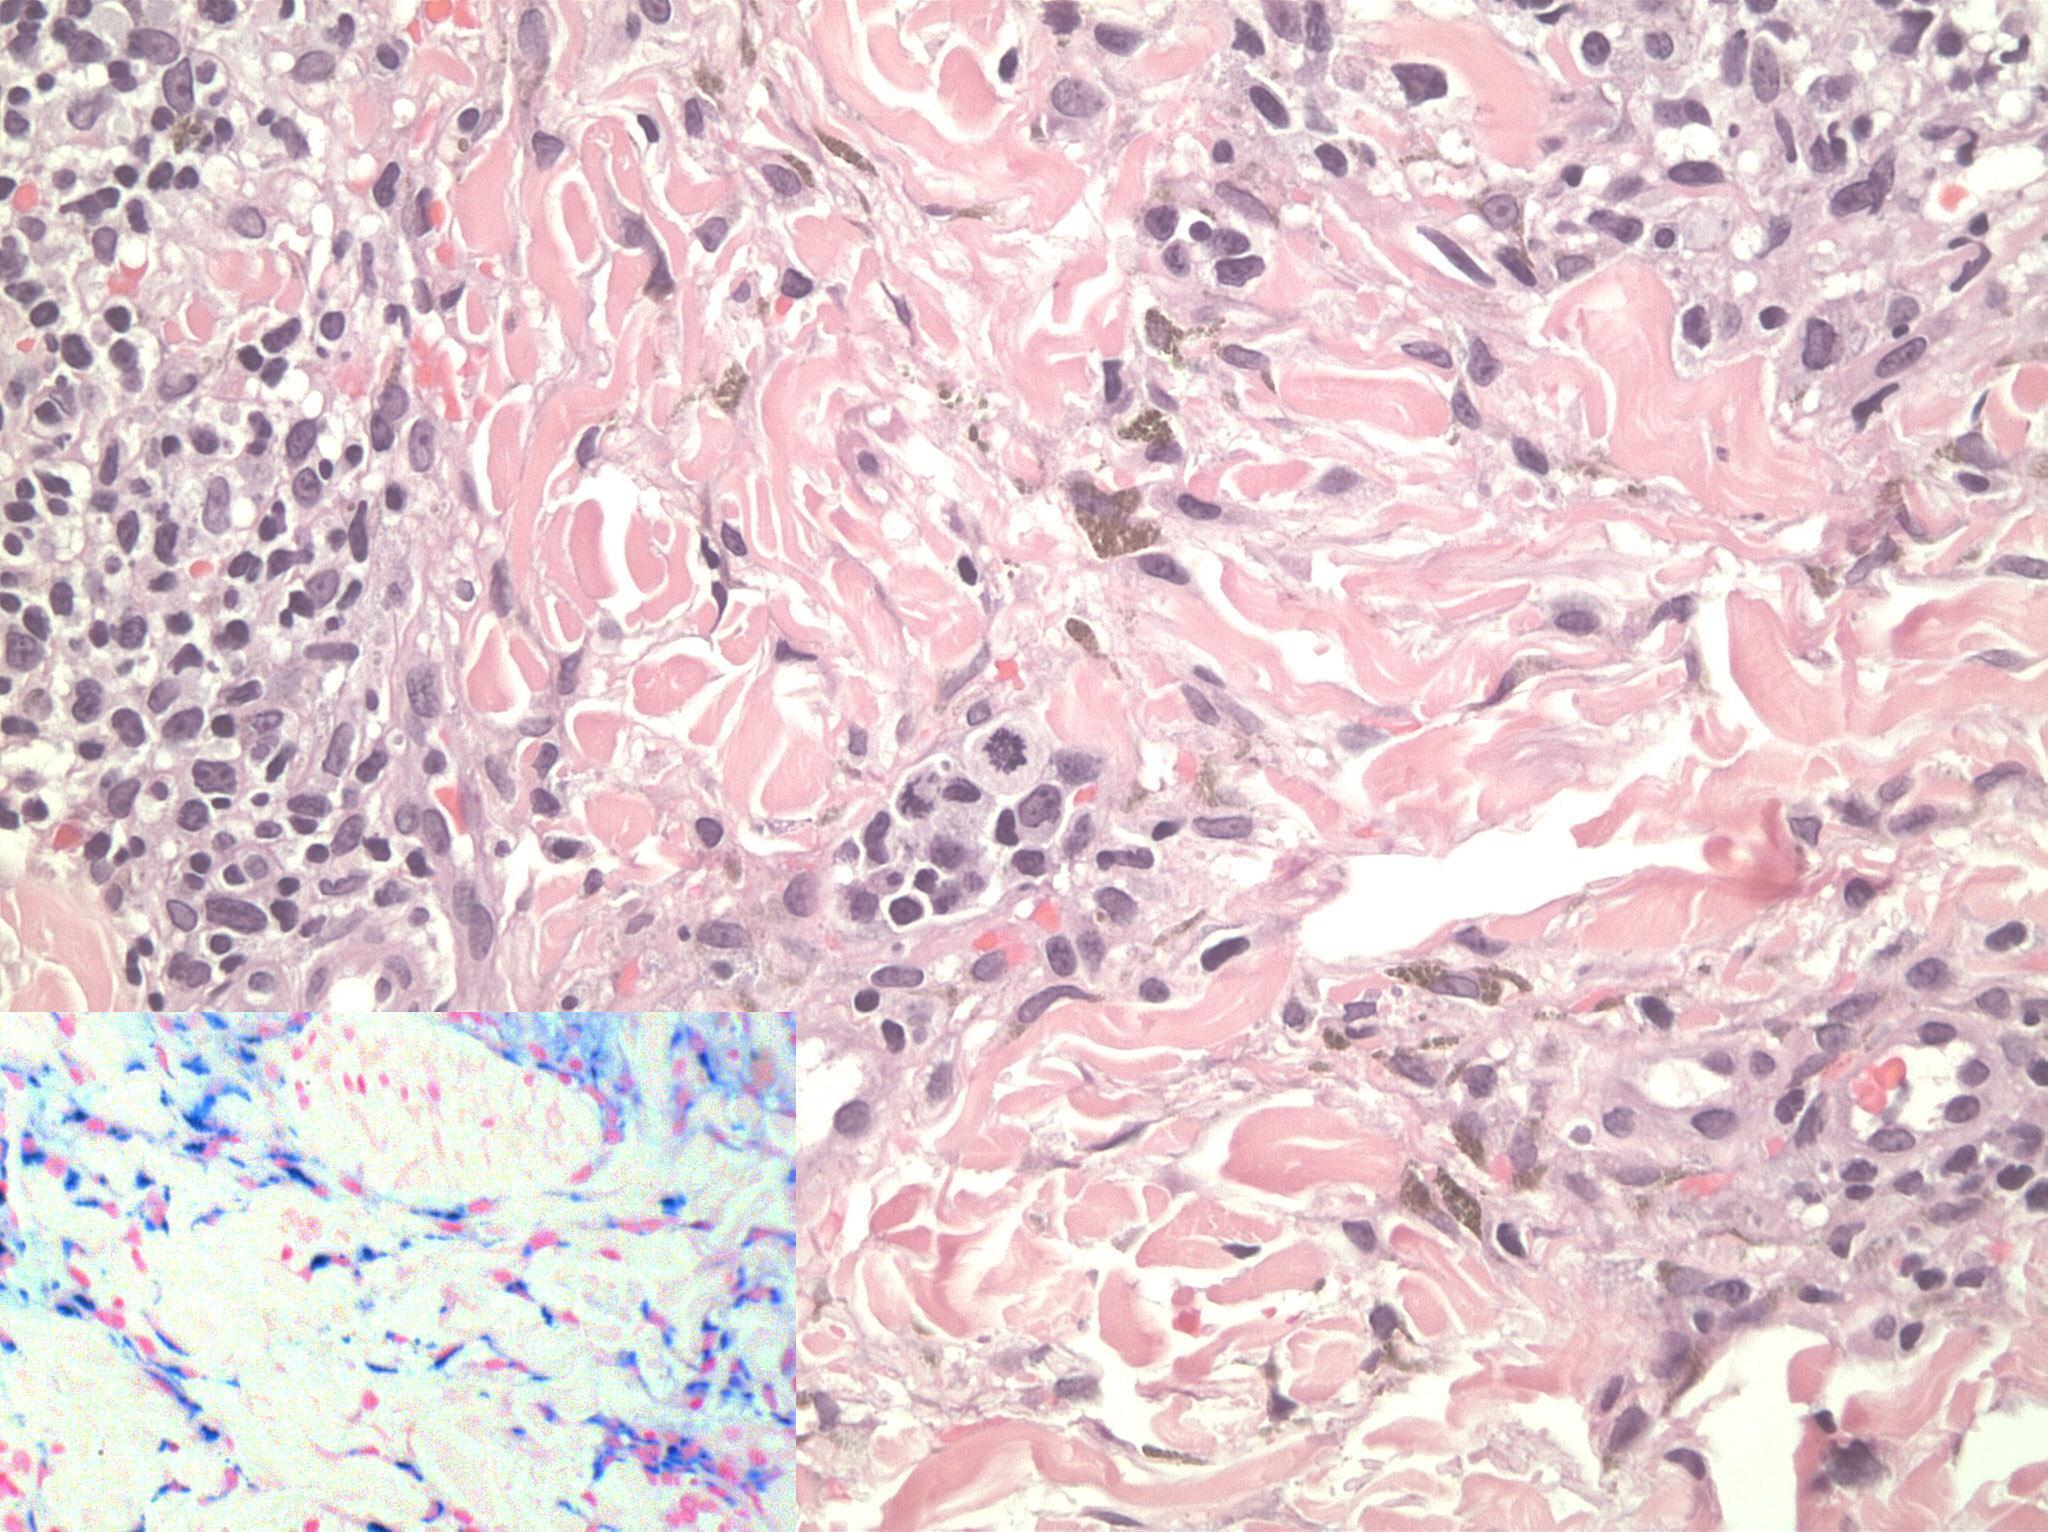

A 30-year-old man presented with a 4-month history of increased facial pigmentation. The patient reported that this had occurred 3 months after being started on oral isotretinoin (40 mg daily) for the treatment of acne vulgaris. He was otherwise healthy and not on any other drug therapy. In addition, he denied using any facial creams at the time when the problem had started. Moreover, he denied family history of similar condition or photodermatosis. On examination, the patient had well-demarcated hyperpigmented patches and plaques on an erythematous purpuric background (Figure 1). The changes were mainly observed on sun exposed surfaces. A punch biopsy was done and revealed dermal lymphohistiocytic infiltrates with scattered eosinophils, extravasated erythrocytes, and prominent hemosiderin deposition highlighted by iron stain (Figure 2). Fontana-Masson stain revealed no increase in melanin in the dermis or epidermis and immunohistochemical staining using MART-1 revealed normal melanocyte number at the basal cell layer of the epidermis.

Figure 2.Histology revealed dermal lymphocytic infiltrates with scattered eosinophils, extravasated erythrocytes, and hemosiderin deposition (original magnification, 20). Inset: Perl’s stain highlights hemosidrin depostion (original magnification, 40).